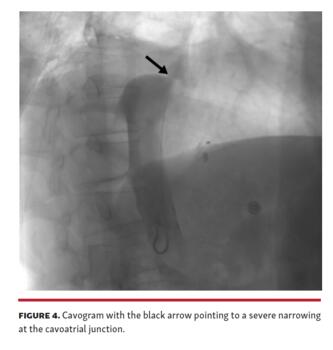

A transjugular liver biopsy and portal pressure measurements were recommended. Mean right atrial (RA) pressure was 16 mm Hg, and mean IVC and free hepatic vein pressures were 21 mm Hg, while mean hepatic vein wedge pressure was 24 mm Hg (Figure 2 and Figure 3). Because no significant gradient should be present across either the superior or inferior cavoatrial junction, we performed IVC angiography. This showed severe narrowing of the cavoatrial junction (Figure 4). Histologic examination of the liver biopsy tissue showed centrilobular sinusoidal dilation and perisinusoidal fibrosis, consistent with venous outflow obstruction (Figure 5). The patient subsequently underwent IVC balloon angioplasty with resolution of the RA-IVC gradient (Figure 6) and without caval or atrial injury.